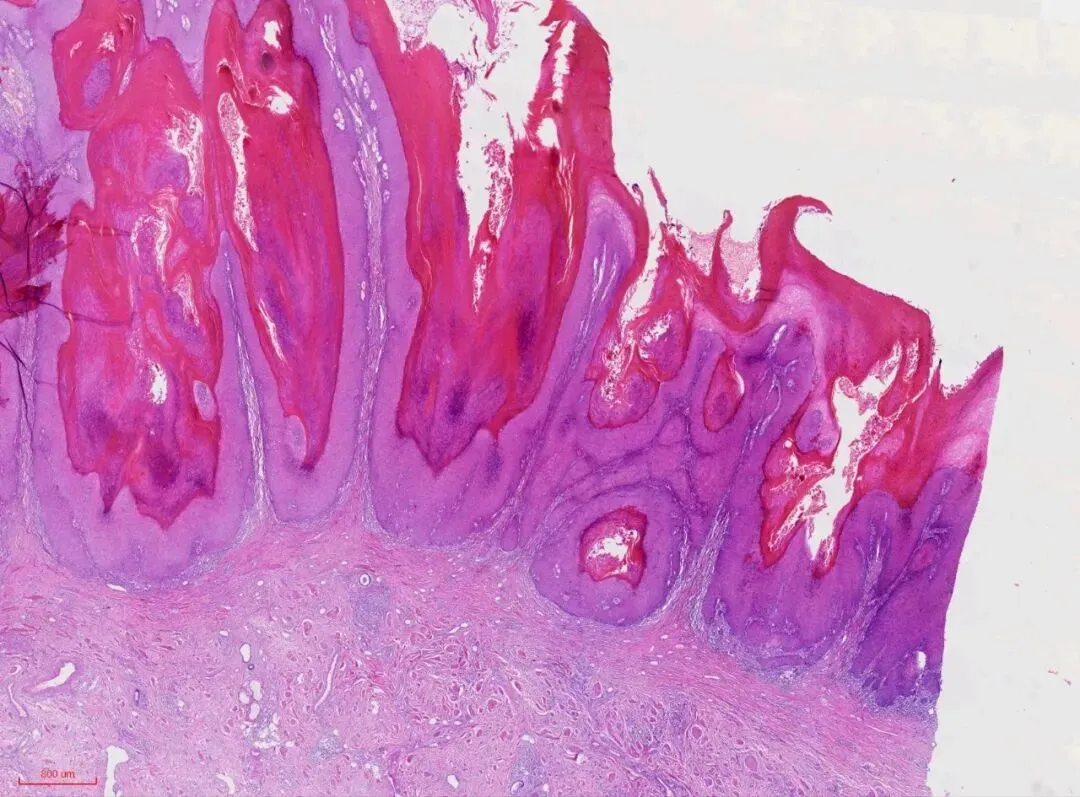

最近遇到一例外阴肿物,肿物比较大,直径约4cm,菜花状,表面有溃疡。显微镜下表现为鳞状上皮增生,呈宽带状延伸并形成乳头状生长模式,纤维血管轴心无或纤细,乳头表面有角化过度和角化不全。如下图

上皮脚粗大,呈圆形或棍棒样,推挤式浸润,如下图。

1.鳞状上皮增生,呈宽带状延伸并形成乳头状生长,纤维血管轴心无或纤细,乳头表面有角化过度和角化不全。棘层明显增厚,上皮角粗大,呈球状或棍棒样挤压推入上皮下间质。